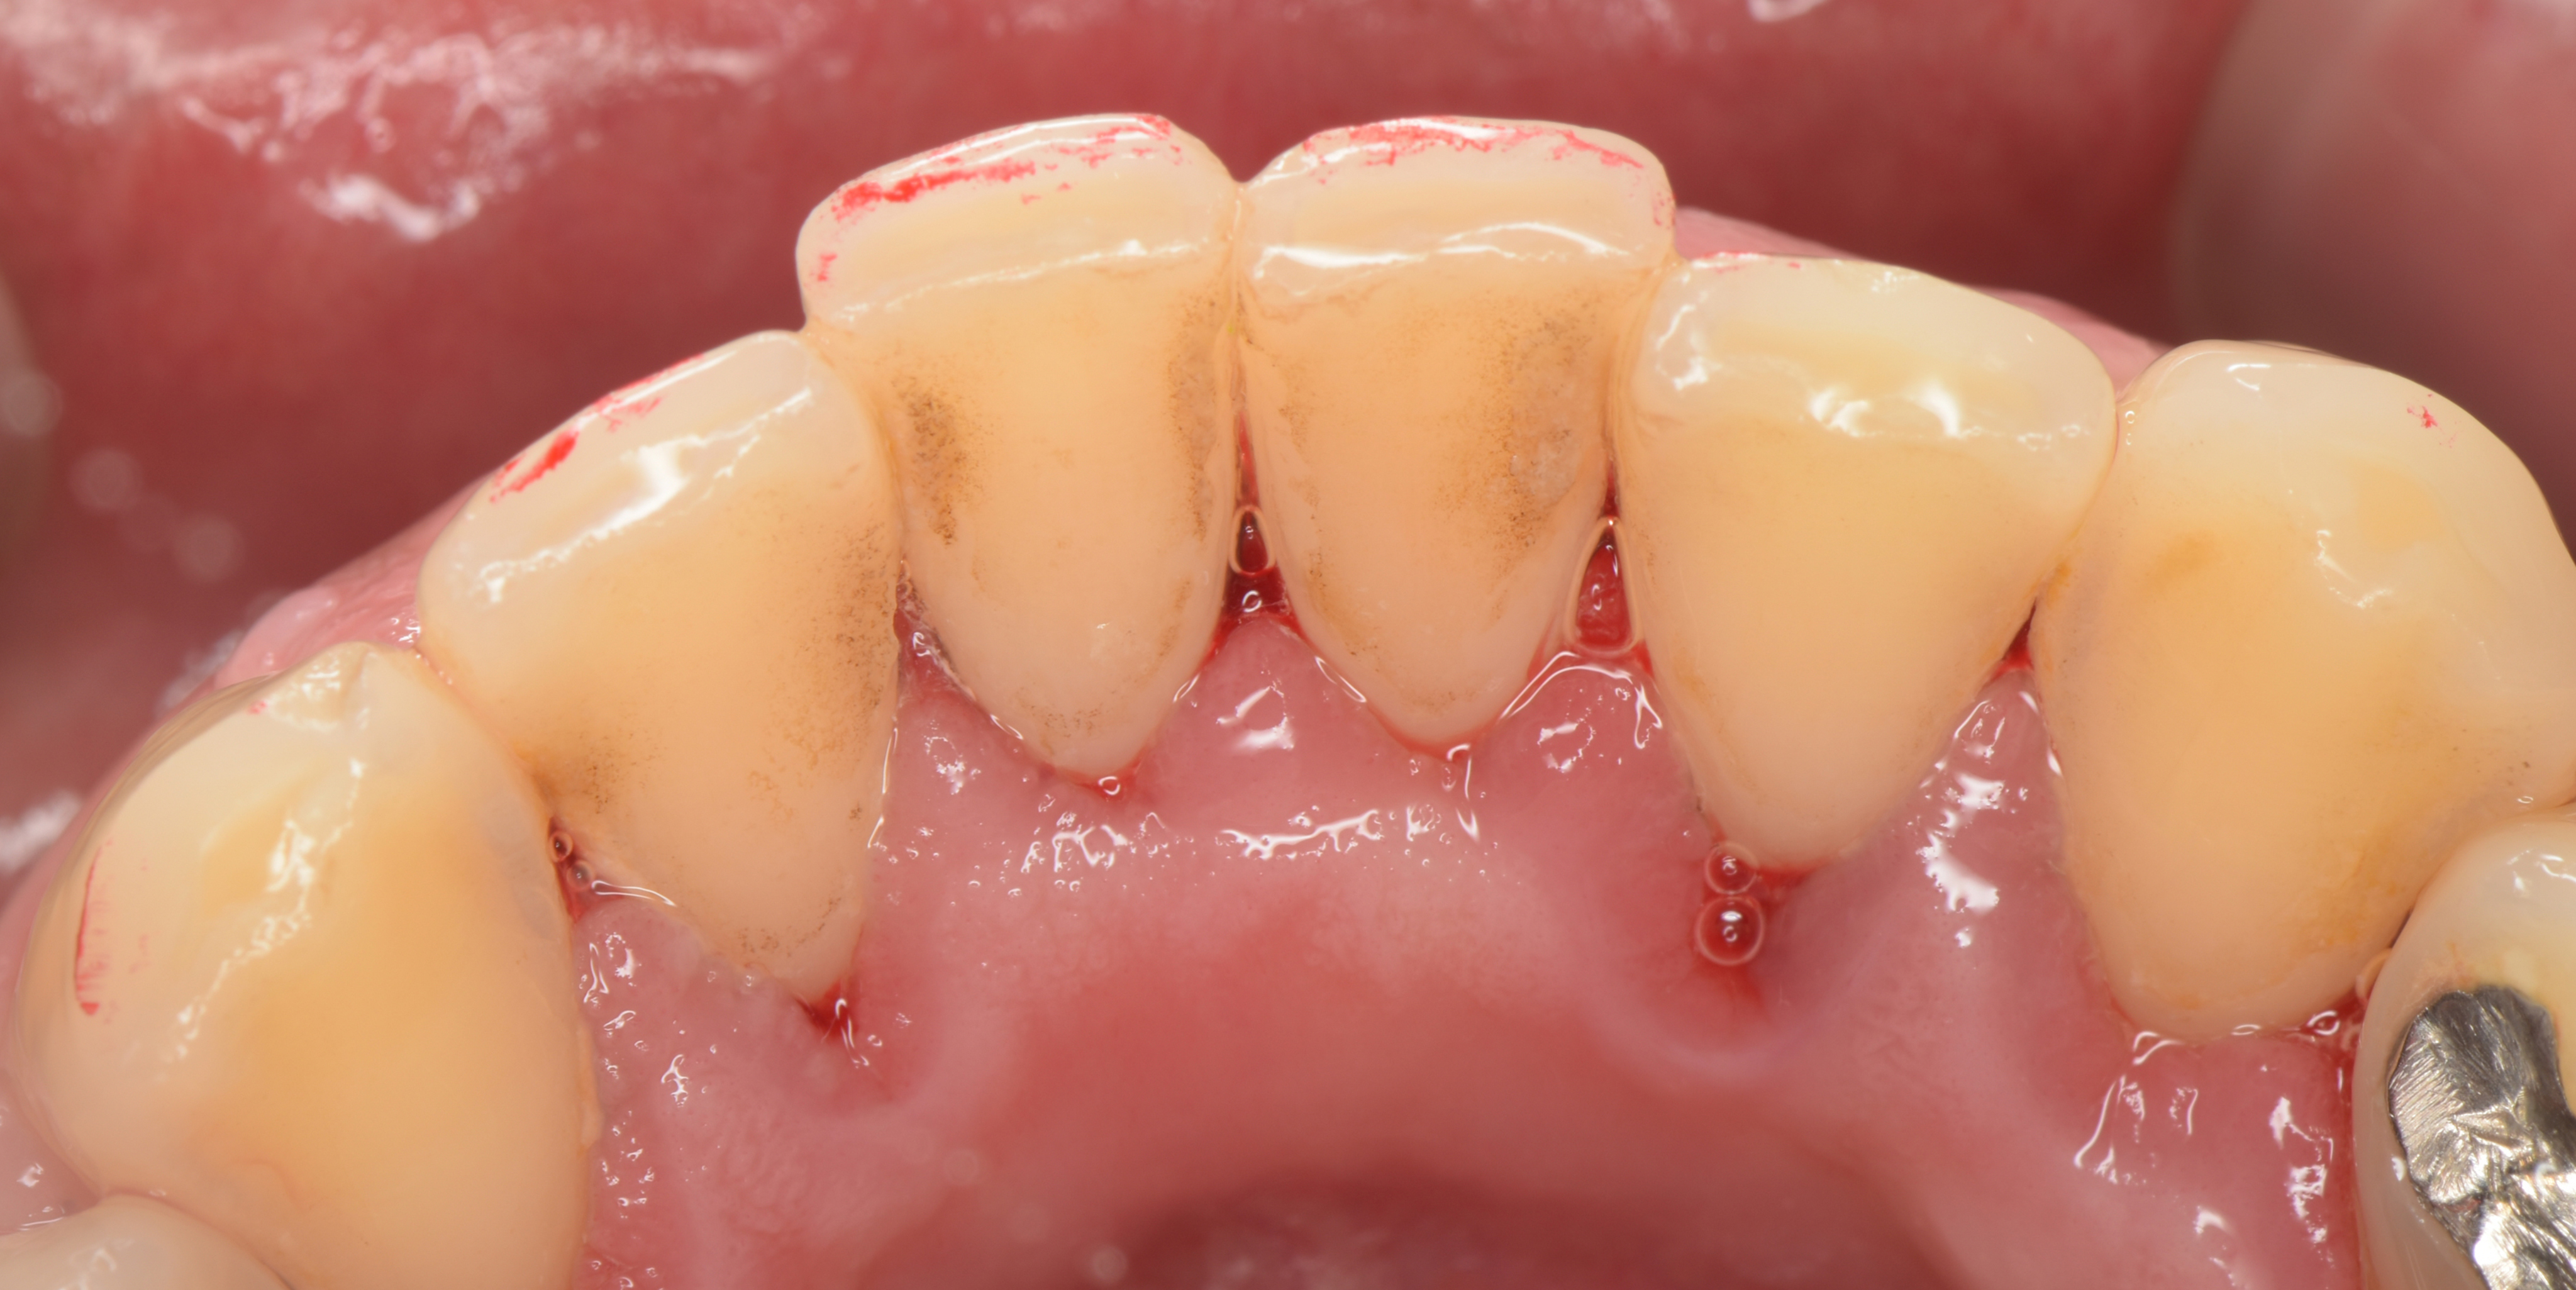

歯石の除去直後の状態

歯石に隠れていた歯肉が見えるようになりました。

歯石と接していた歯肉が赤く腫れているのが見てとれます。